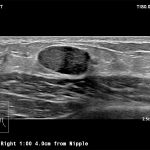

Imagini clinice:

Aplicatii: